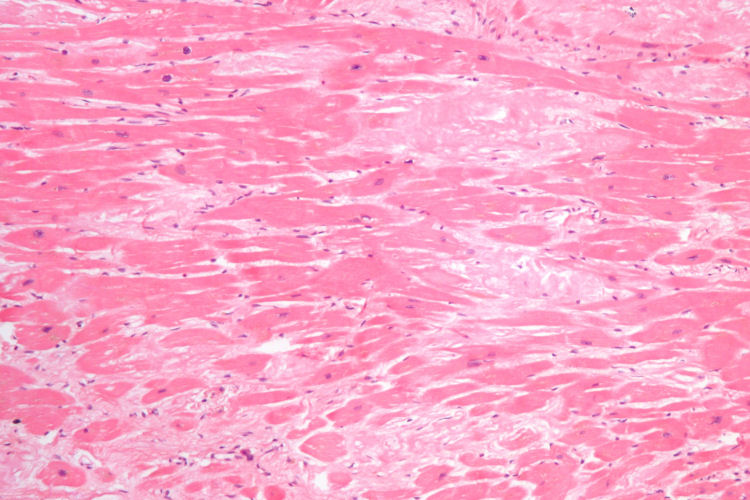

back cardiac amyloidosis

Source: Cardiac amyloidosis intermed mag he.jpg